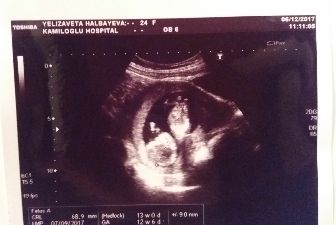

Вот и прошли мы первый скрининг ( на сроке 12.6 недель). По узи срок 13 недель ровно. Увидела малышика, пол сказали пока рано определять… В 17 недель хочу сходить еще раз пол посмотреть. А так все у нас хорошо ?